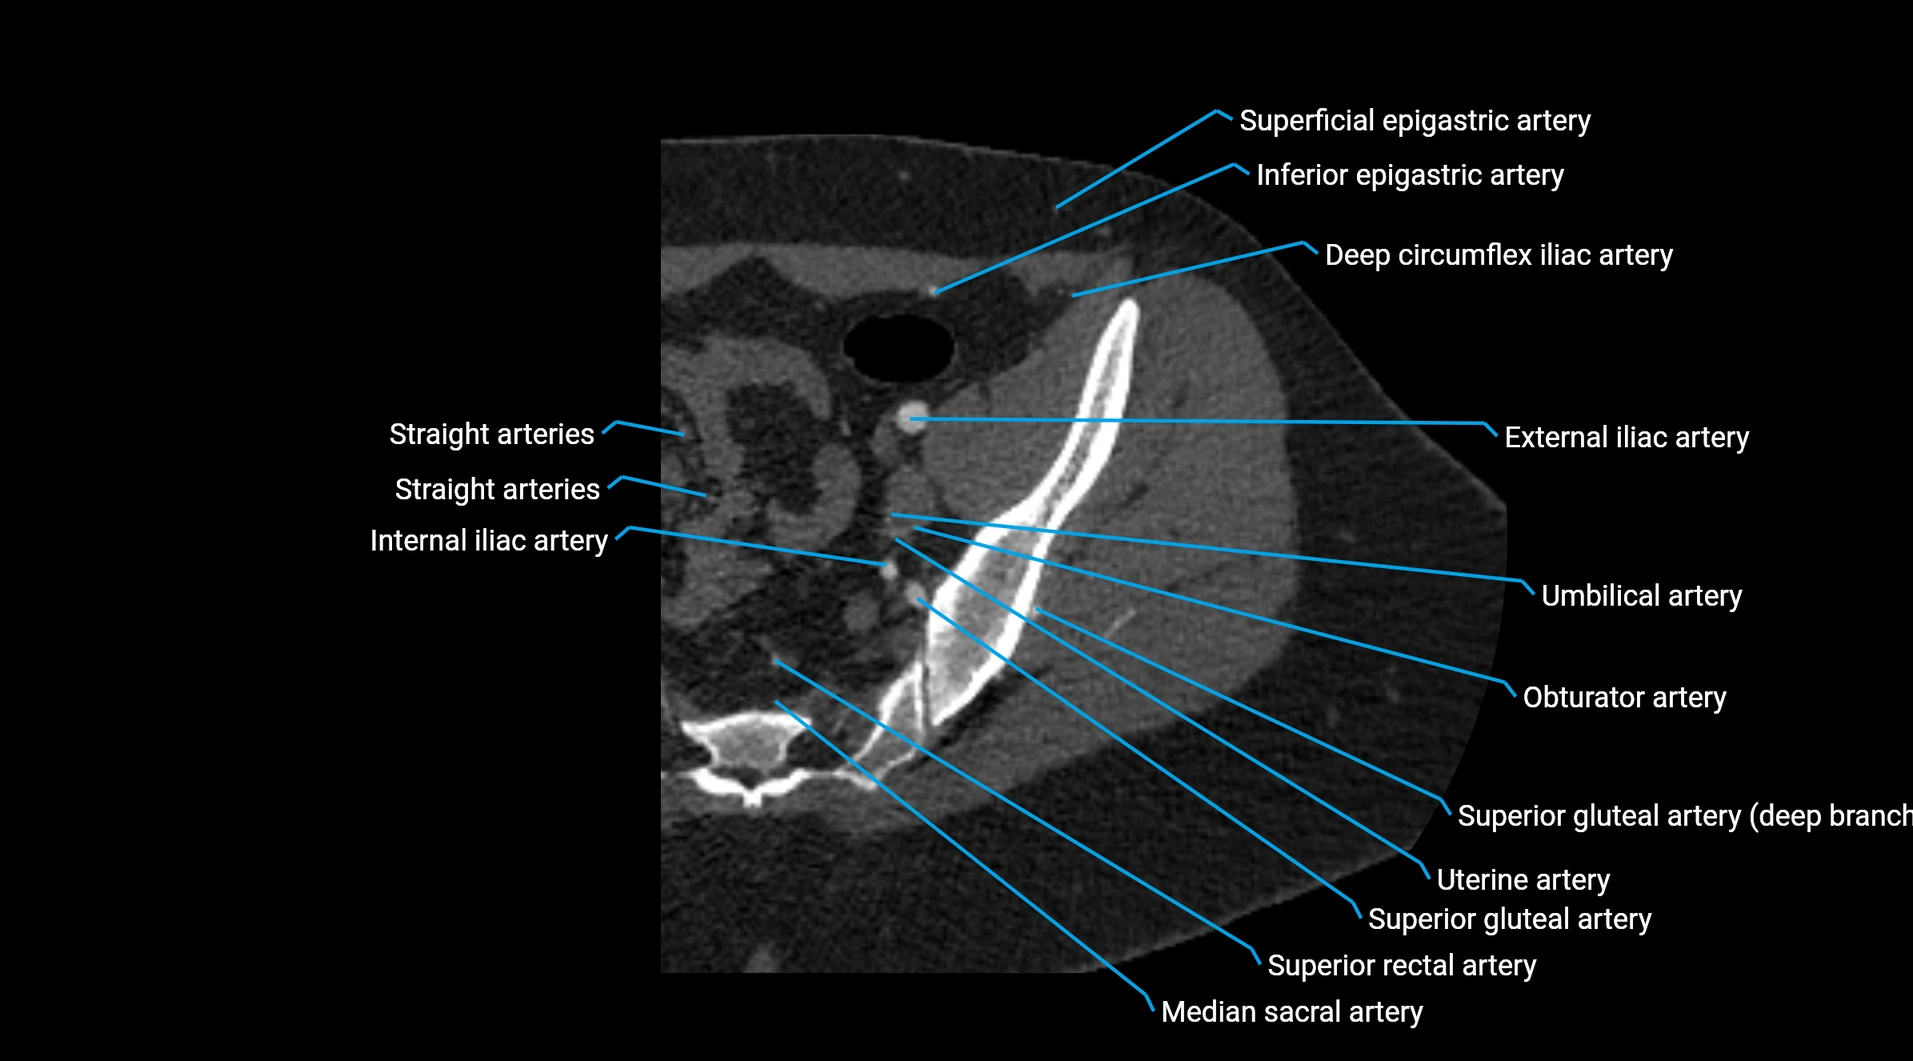

Contrast-enhanced CT (CTA):

• Gold standard for abdominal aortic imaging

• Provides excellent detail of lumen, wall, aneurysm, thrombus, and branch vessels

• Multiplanar and 3D reconstructions help in aneurysm measurement, stent graft planning, and dissection evaluation

CT images

image